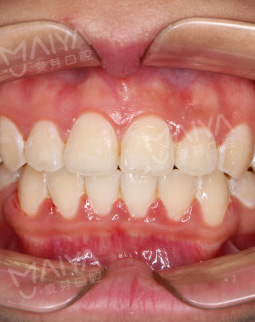

2017/05/30 矫正完成

最后的最后,矫治器,“一半靠医生,一半靠自己”。在麦芽我看到很多二次矫正的案例,都是因为没有戴保持器,我觉得我很听话,为了美为了自己,医生说可能要戴个一两年,后戴的时间会越来越短,后面就应该完全可以脱离了~~想想很合算,矫牙一两年幸福一辈子,辛苦点又算的了什么?矫牙变美我做到了,我预祝更多的宝宝都能有个整齐的牙齿变成美美的自己,人间值得!!!

幼儿园的小朋友更愿意和我亲近了,说喜欢何老师上的课,喜欢和何老师玩~~~很多人问我是不是参加了“变形记”,有的人还问我在哪里整容的,脸型怎么这么好卡性格比之前更开朗了!其实我只是牙齿参加了变形记,矫牙美脸说的就是我了,没有整容!一年前有多伤心有多苦恼,今天笑的就有多开心!未来,我会一直坚持做一名园丁,为更多的小朋友带去欢乐~~~